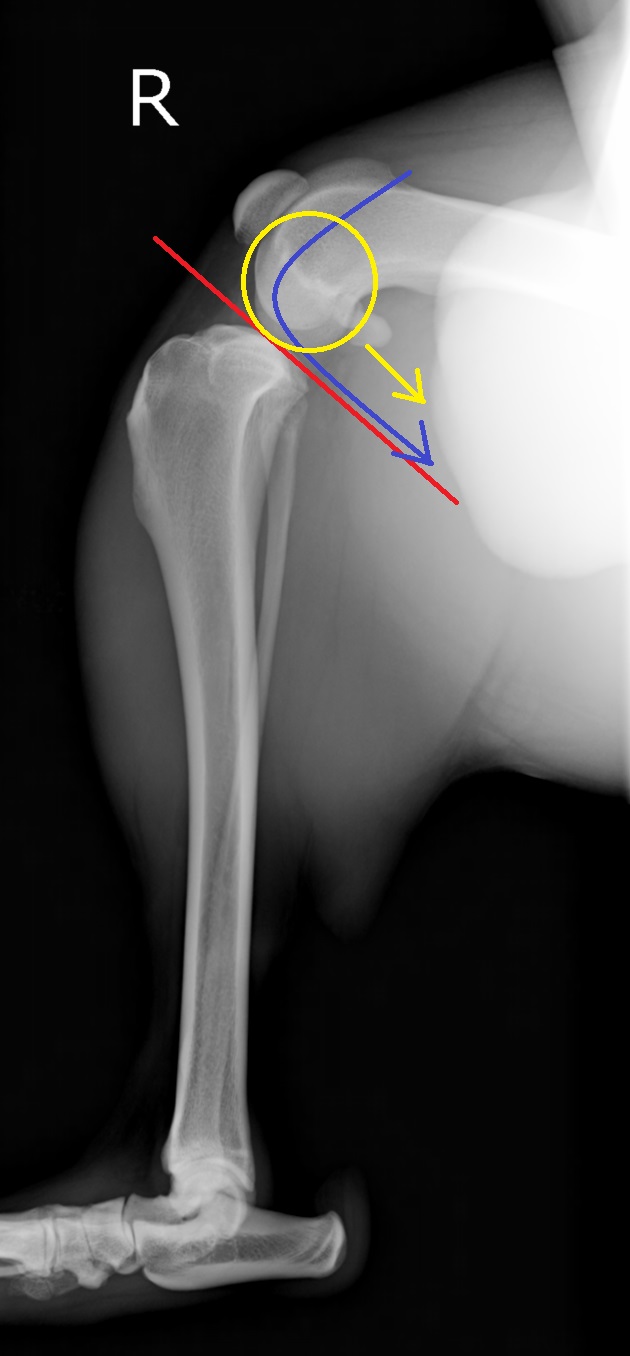

赤直線が脛骨高平部角、青・黄色矢印は大腿骨が滑り落ちてしまう力のベクトル

前十字靭帯損傷の膝。大腿骨が尾側に滑り、脛骨の前方変位が認められる